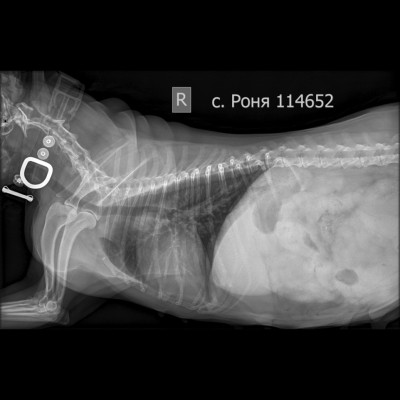

Рентген в двух проекциях и бак посев из раны

Вложения

IMG_20251130_193642_149.jpg

IMG_20251130_193646_292.jpg